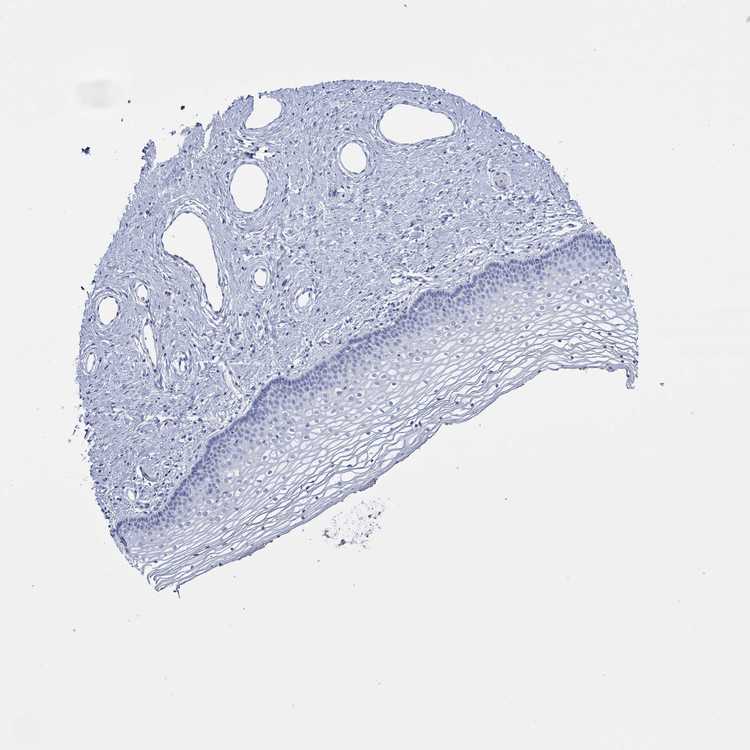

TISSUE PRIMARY DATA VAGINA Show tissue menu

VAGINA - Antibody stainingi

Antibody staining in the annotated cell types in the current human tissue is reported as not detected, low, medium, or high, based on conventional immunohistochemistry profiling in selected tissues. This score is based on the combination of the staining intensity and fraction of stained cells.

Each image is clickable and will lead to virtual microscopy that enables deeper exploration of all samples and also displays staining intensity scores, fraction scores and subcellular localization as well as patient and tissue information for each sample.

Antibody HPA008005Antibody HPA075088

Squamous epithelial cells LowNot detected